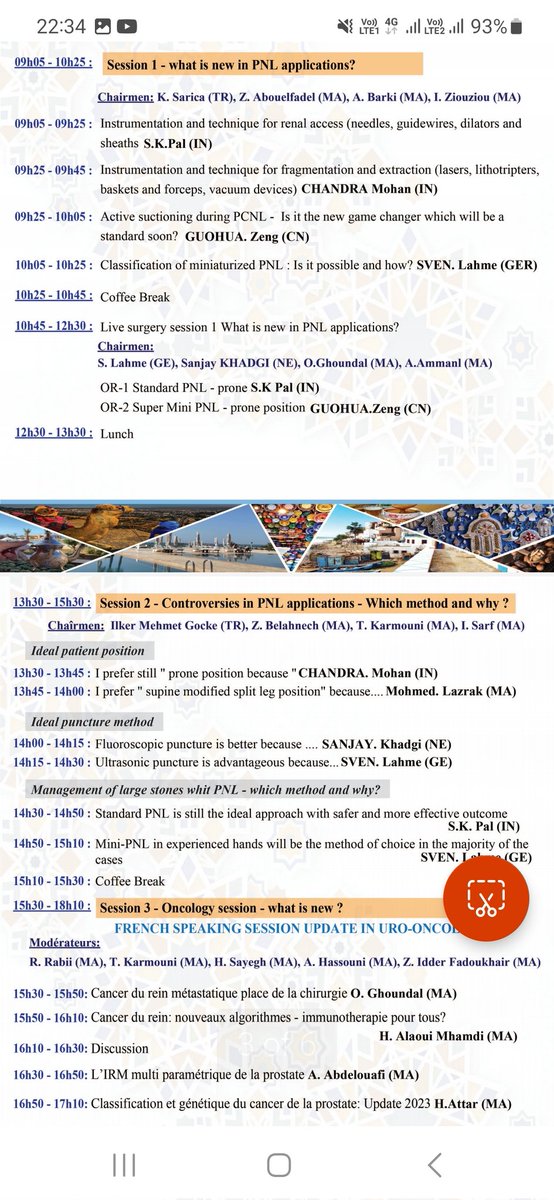

Great beginning to the 12th IAU annual conference. Well attended truly international master class arranged by Simon Choong Kemal Sarıca Shashi Kiran Pal Clare Allen, #Zeng Guohua RSM Urology Section